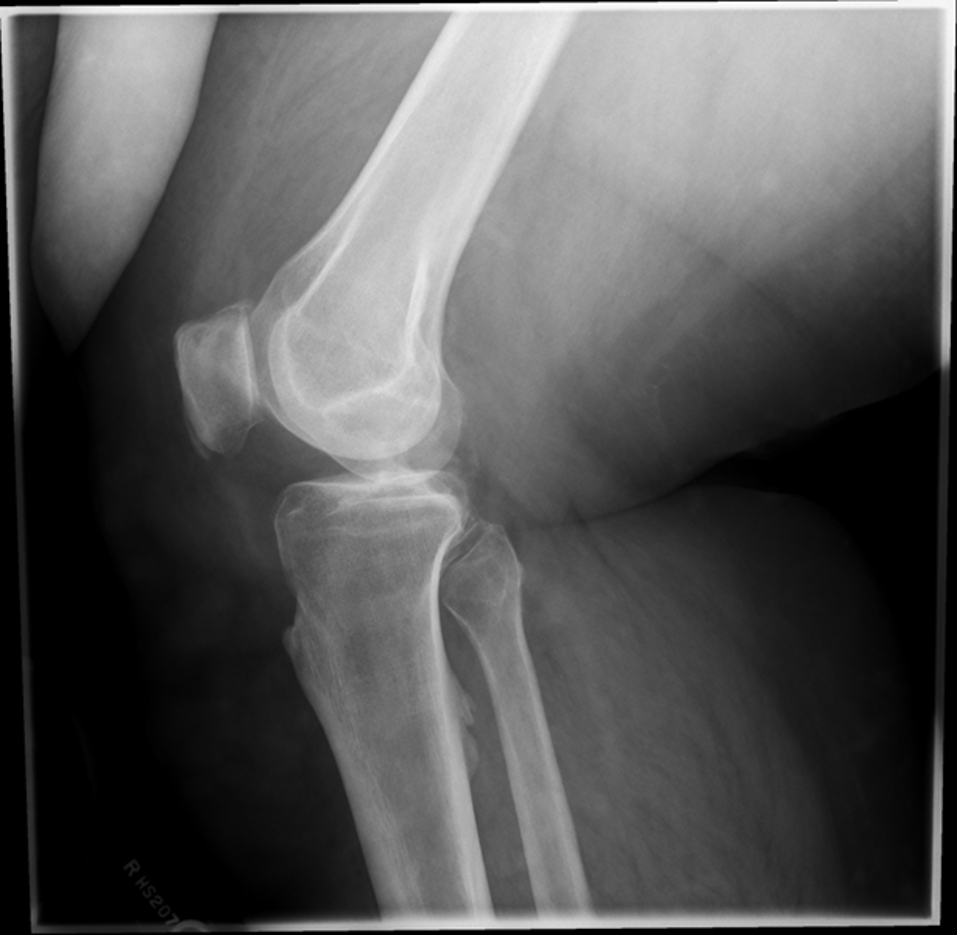

20 to 30 degrees

at what anlge should the patient’s knee be flex ed to get a good lateral of a knee?

over rotated

if the medial condyle is closer to the patella in a lateral knee, what is the image critique?

under rotated

if the lateral condyle is closer to the patella in a lateral knee, what is the image critique?

what is the image critique for this lateral knee?